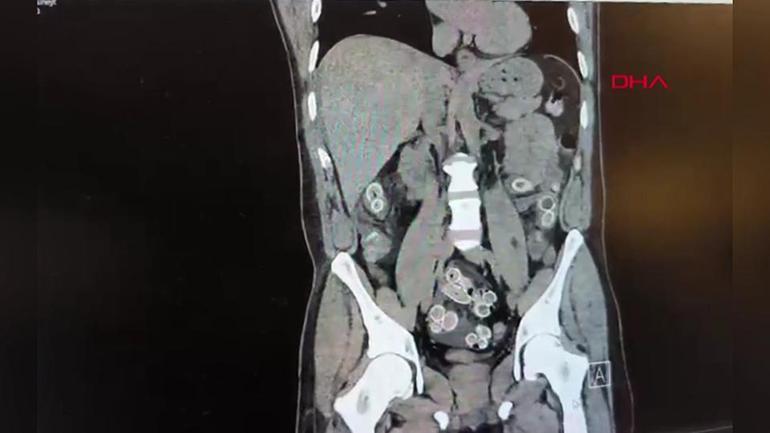

Hastane yetkilileri durumu polise ekiplerine bildirdi. Hızla ameliyata alınan şüphelinin midesinden 49 adet paketlenmiş, toplam 259 gram ağırlığında uyuşturucu madde çıkarıldı.